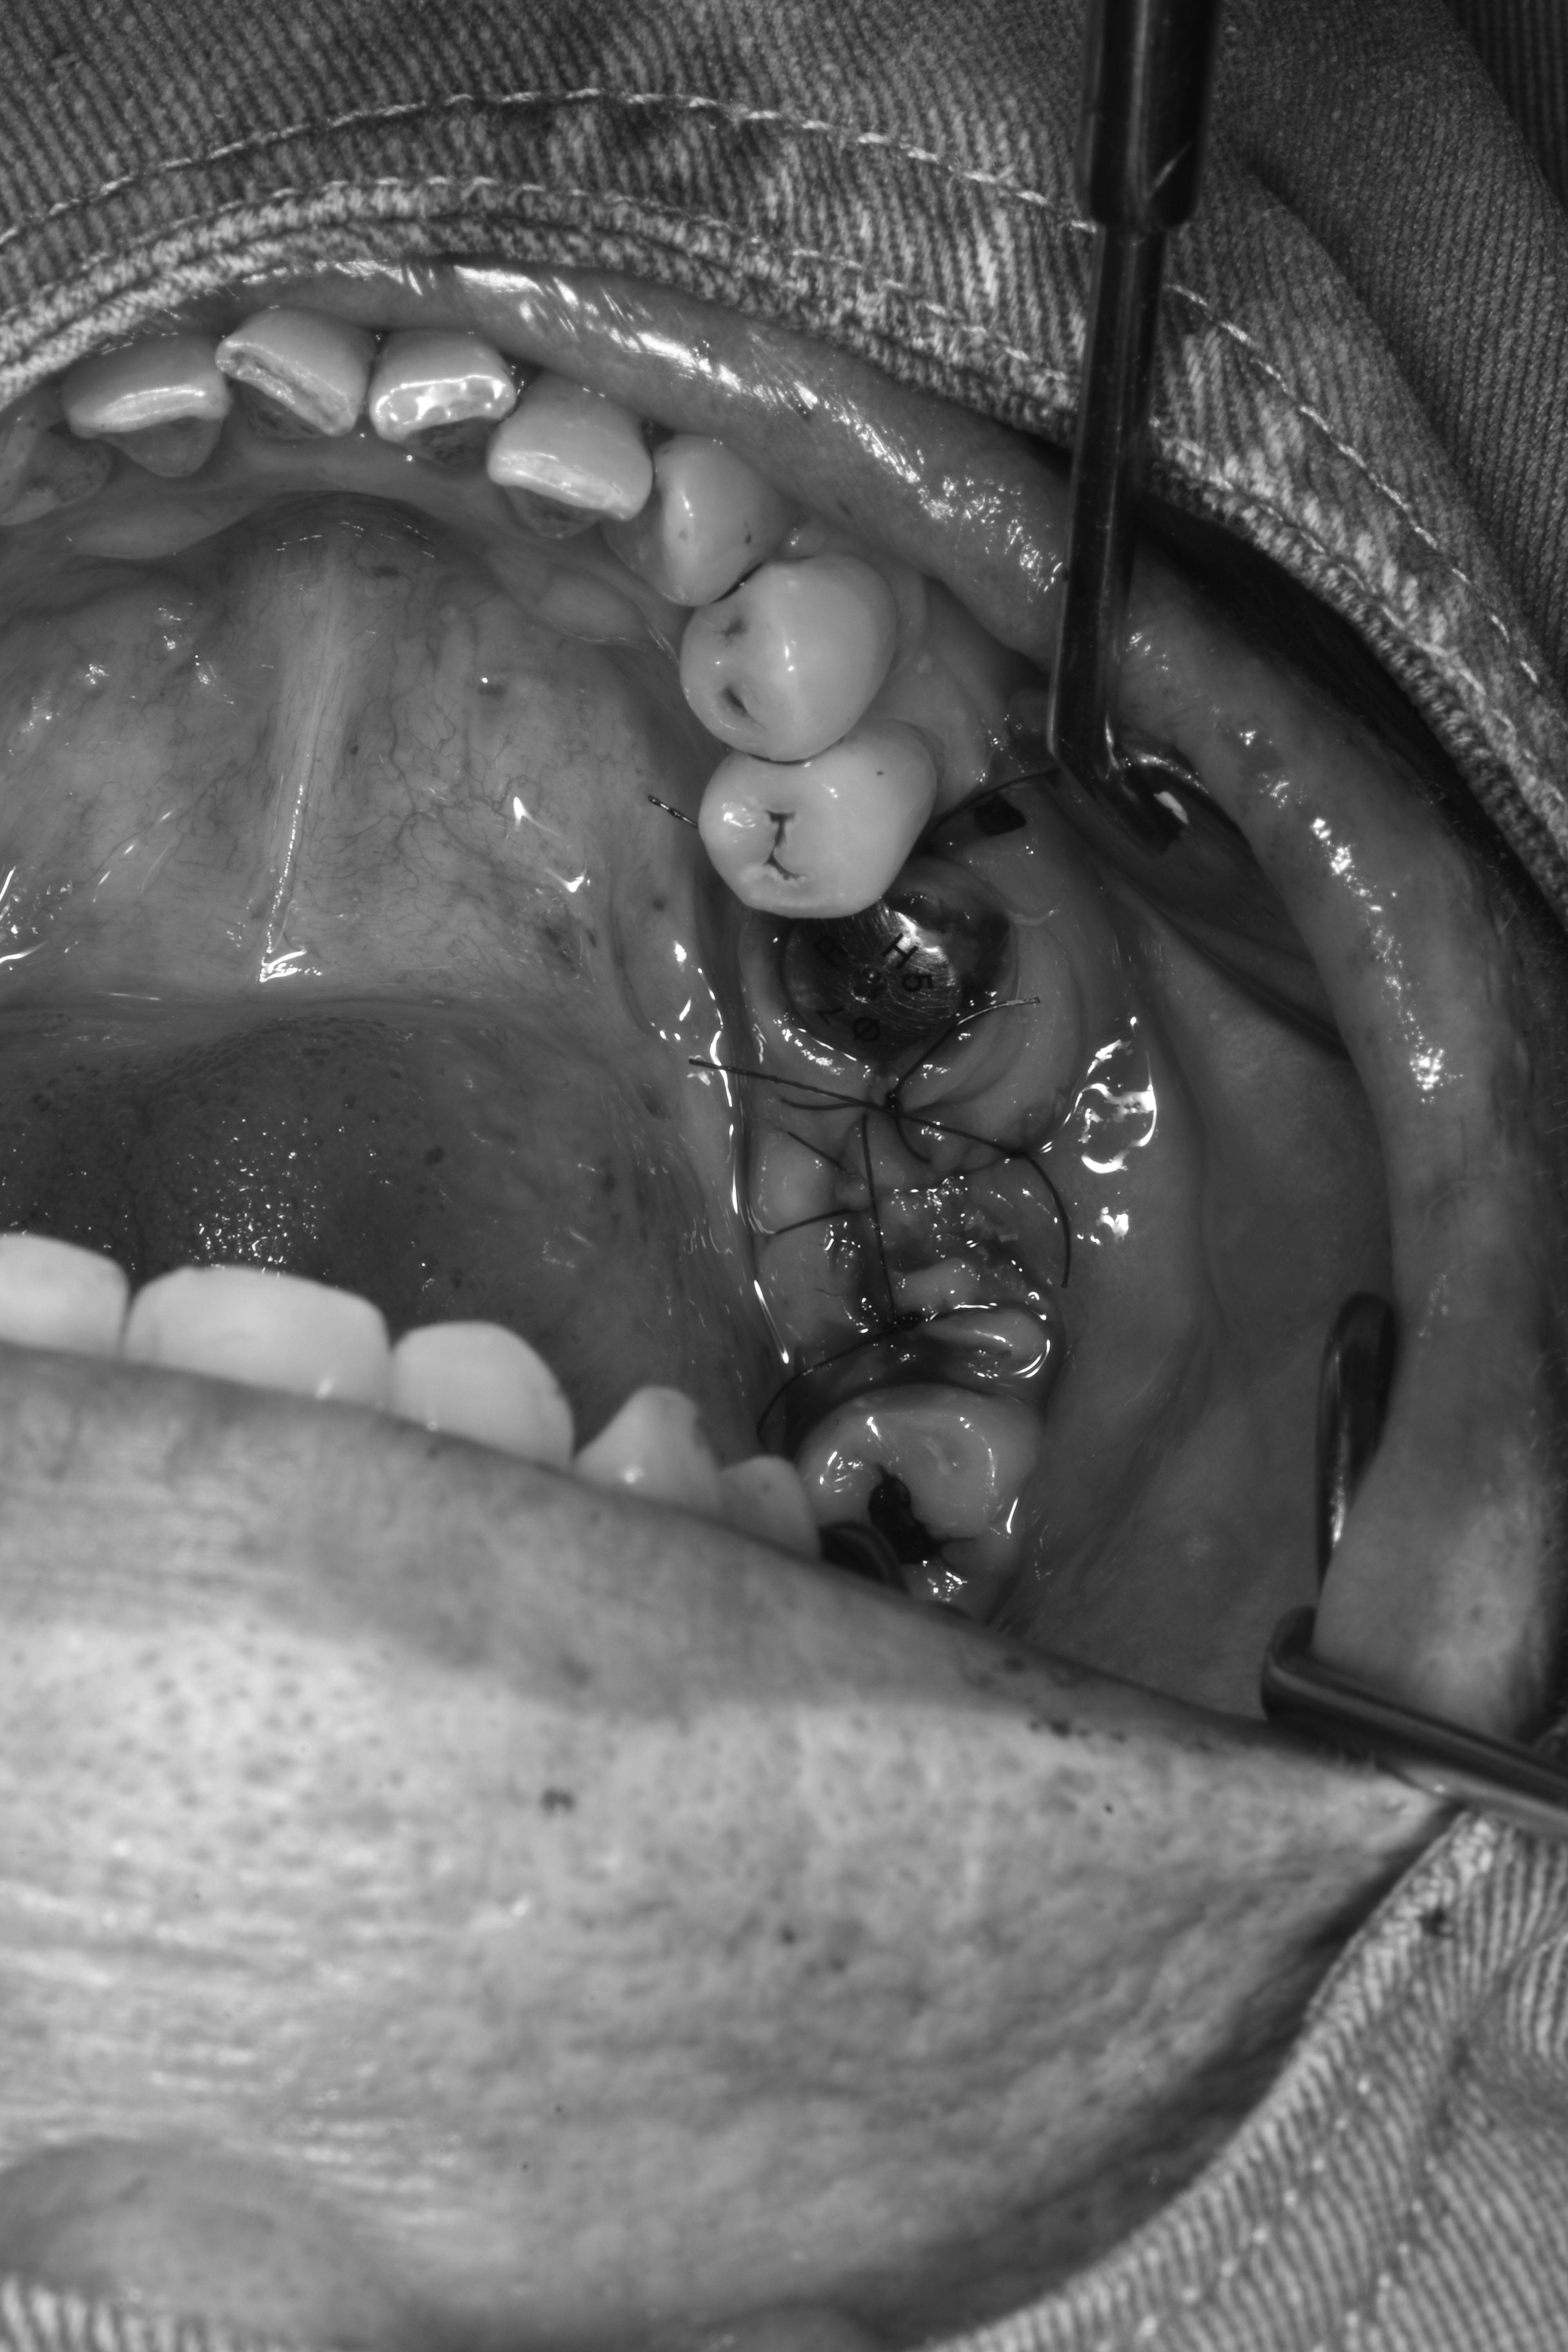

齒槽骨保存術(拔完牙立即補骨)